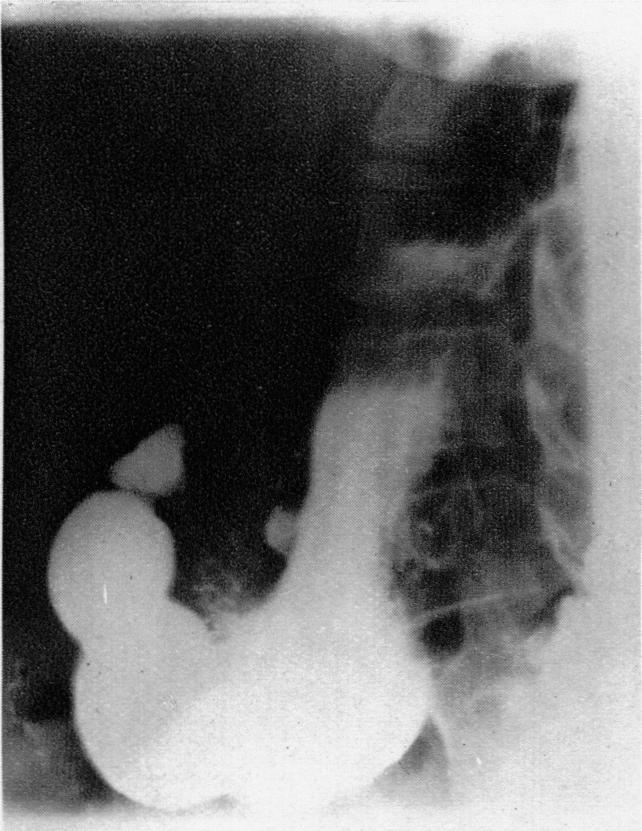

Carcinoma of the Stomach.

Br Med J. 1937 Nov 13;2(4010):949-978.1. doi: 10.1136/bmj.2.4010.949.